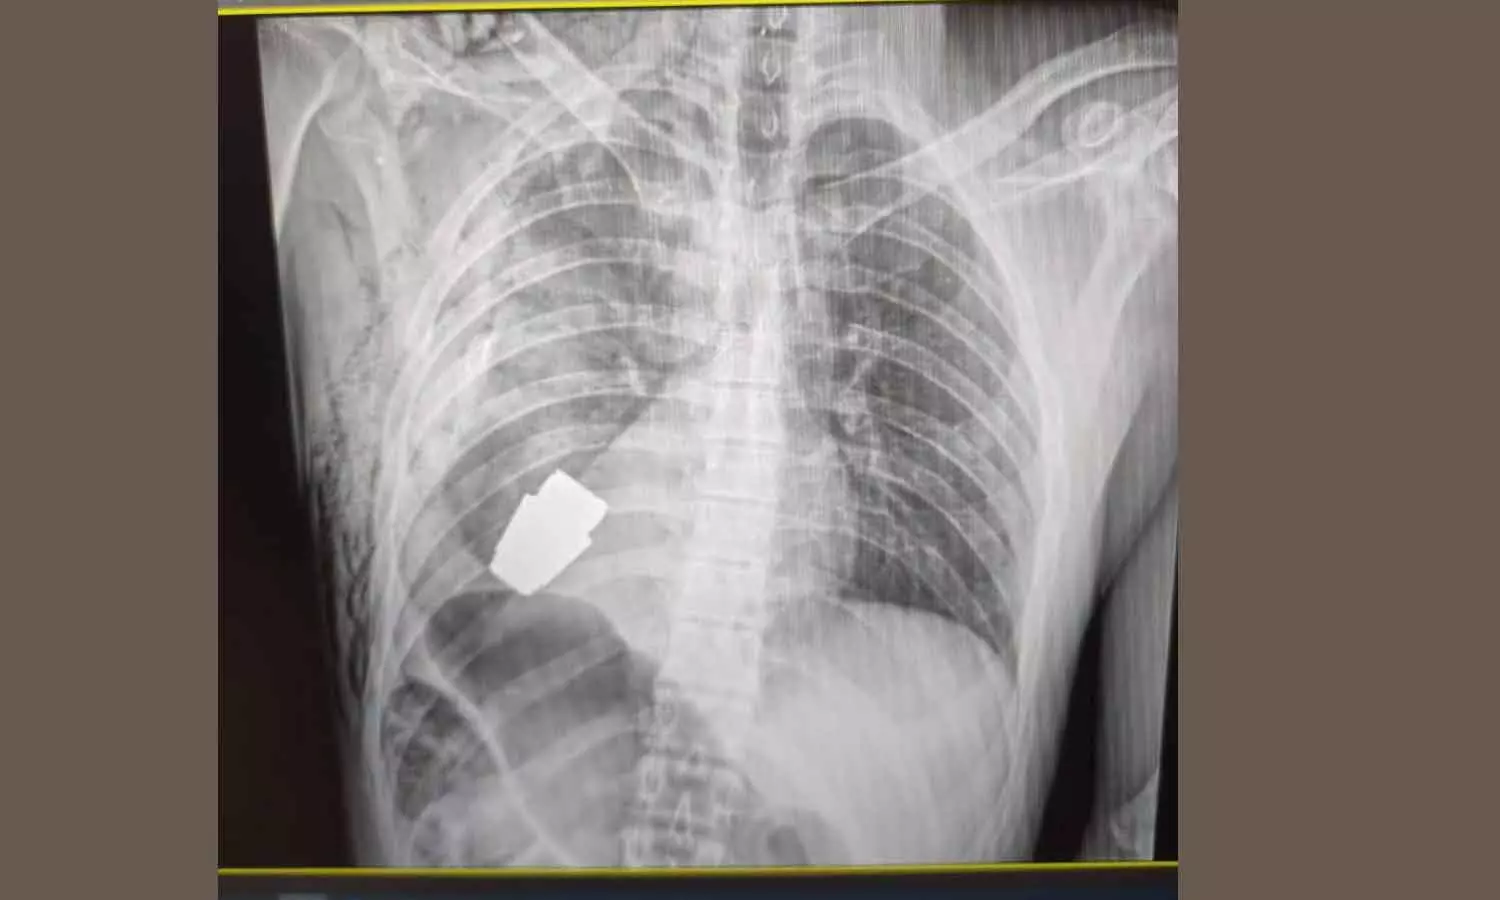

യുക്രൈൻ സൈനികന്റെ നെഞ്ചിൽ തുളഞ്ഞുകയറിയ പൊട്ടാത്ത ഗ്രനേഡ് ശസ്ത്രക്രിയയിലൂടെ നീക്കി

ഹൃദയത്തിന്റെ തൊട്ടുതാഴെ തുളഞ്ഞുകയറിയ ഗ്രനേഡ് സൈനിക സർജൻമാർ വളരെ സങ്കീർണമായ ശസ്ത്രക്രിയയിലൂടെയാണ് പുറത്തെടുത്തത്.

കിയവ്: യുക്രൈൻ സൈനികന്റെ നെഞ്ചിൽനിന്ന് പൊട്ടാത്ത ഗ്രനേഡ് ശസ്ത്രക്രിയയിലൂടെ നീക്കം ചെയ്തു. ഹൃദയത്തിന്റെ തൊട്ടുതാഴെ തുളഞ്ഞുകയറിയ ഗ്രനേഡ് സൈനിക സർജൻമാർ വളരെ സങ്കീർണമായ ശസ്ത്രക്രിയയിലൂടെയാണ് പുറത്തെടുത്തത്.

''ഞങ്ങളുടെ സൈനിക ഡോക്ടർമാർ പൊട്ടാത്ത വി.ഒ.ജി ഗ്രനേഡ് സൈനികന്റെ ശരീരത്തിൽനിന്ന് നീക്കം ചെയ്തു. ഡോക്ടർമാരുടെയും രോഗിയുടെയും സുരക്ഷ ഉറപ്പാക്കുന്നതിനായി രണ്ട് സ്‌ഫോടക വസ്തു വിദഗ്ധൻമാരുടെ സാന്നിധ്യത്തിലാണ് ശസ്ത്രക്രിയ നടത്തിയത്''-യുക്രൈൻ സൈന്യത്തിന്റെ ജനറൽ സ്റ്റാഫ് ഫേസ്ബുക്കിൽ കുറിച്ചു.

ഗ്രനേഡ് പൊട്ടിത്തെറിക്കാൻ സാധ്യതയുള്ളതിനാൽ ഇലക്ട്രോകൊഗുലേഷൻ ഇല്ലാതെയാണ് ശസ്ത്രക്രിയ നടത്തിയത്. ശസ്ത്രക്രിയക്കിടെ വൈദ്യുതി ഉപയോഗിച്ച് രക്തയോട്ടം താൽക്കാലികമായി നിർത്തുന്ന പ്രക്രിയയാണ് ഇലക്ട്രോകൊഗുലേഷൻ.